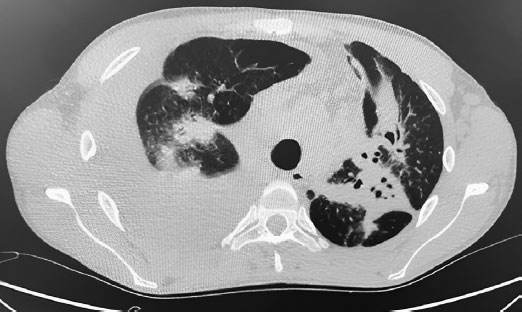

Рис. 1. КТ органов грудной полости (ОГП) от 31.05.2022 г.

КТ органов грудной полости (ОГП) от 31.05.2022 г.: Трахея и крупные бронхи прослеживаются на всем протяжении, не изменены. Определяются двусторонние массивные инфильтраты в паренхиме обоих легких. Полость деструкции в S9 левого легкого диаметром до 4 мм. Сердце в размерах не увеличено, ширина магистральных сосудов в пределах нормальных значений. Определяются множественные увеличенные лимфатические узлы средостения: паратрахеальные до 17 мм, аортальные до 14 мм, бифуркационные сливаются в конгломерат до 60 × 32 мм.

Заключение: Двусторонние массивные инфильтраты в паренхиме обоих легких. Бронхиолит. Правосторонний плевральный выпот (1600–1800 мл). Смещение средостения влево. Лимфаденопатия средостения, увеличение аксиллярных, субпекторальных ЛУ. КТ-картину следует дифференцировать между двусторонней полисегментарной пневмонией, интерстициальным заболеванием легких и системным заболеванием.